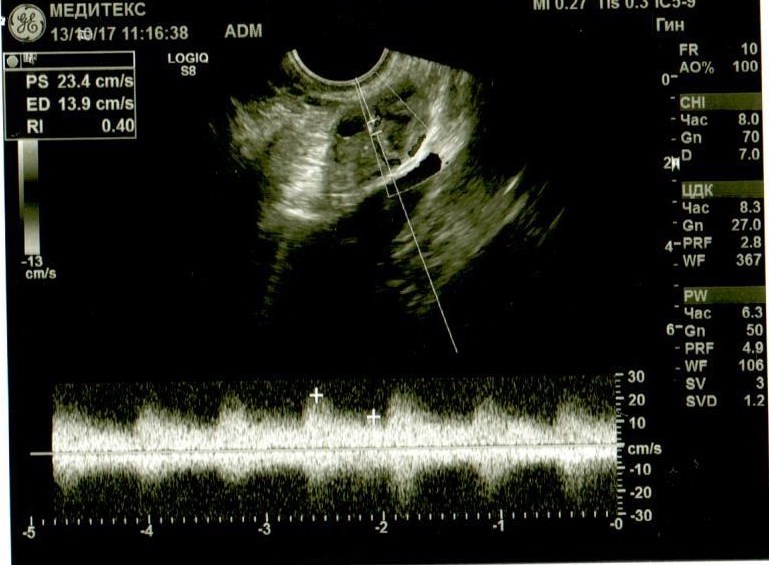

Если можно, посмотрите. Буду очень благодарна. Не очень в этом разбираюсь, поэтому выкладываю все снимки и заключение узистки.

Добрый день! У Вас в самой структуре яичника имеются гиперэхогенные включения, которые говорят о перенесенном воспалении, при этом о спайках может говорить только расположение яичников возле матки ( это если опираться на описание, так как на фото не видно). Однозначно, имеет место хронический оофорит. И в эндометрии мне не нравится зона в области дна. Врач ее даже выделила, но не описала. Эндометрий неоднородный, стоит сделать УЗИ на 5 день цикла повторно.